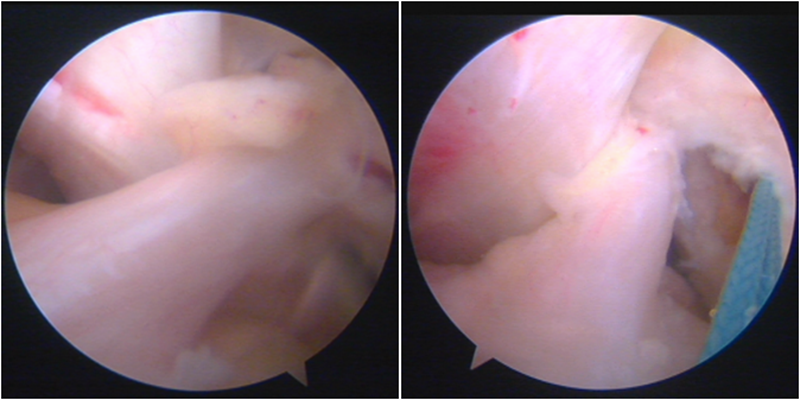

镜下显示ACL残束

内侧半月板

外侧半月板